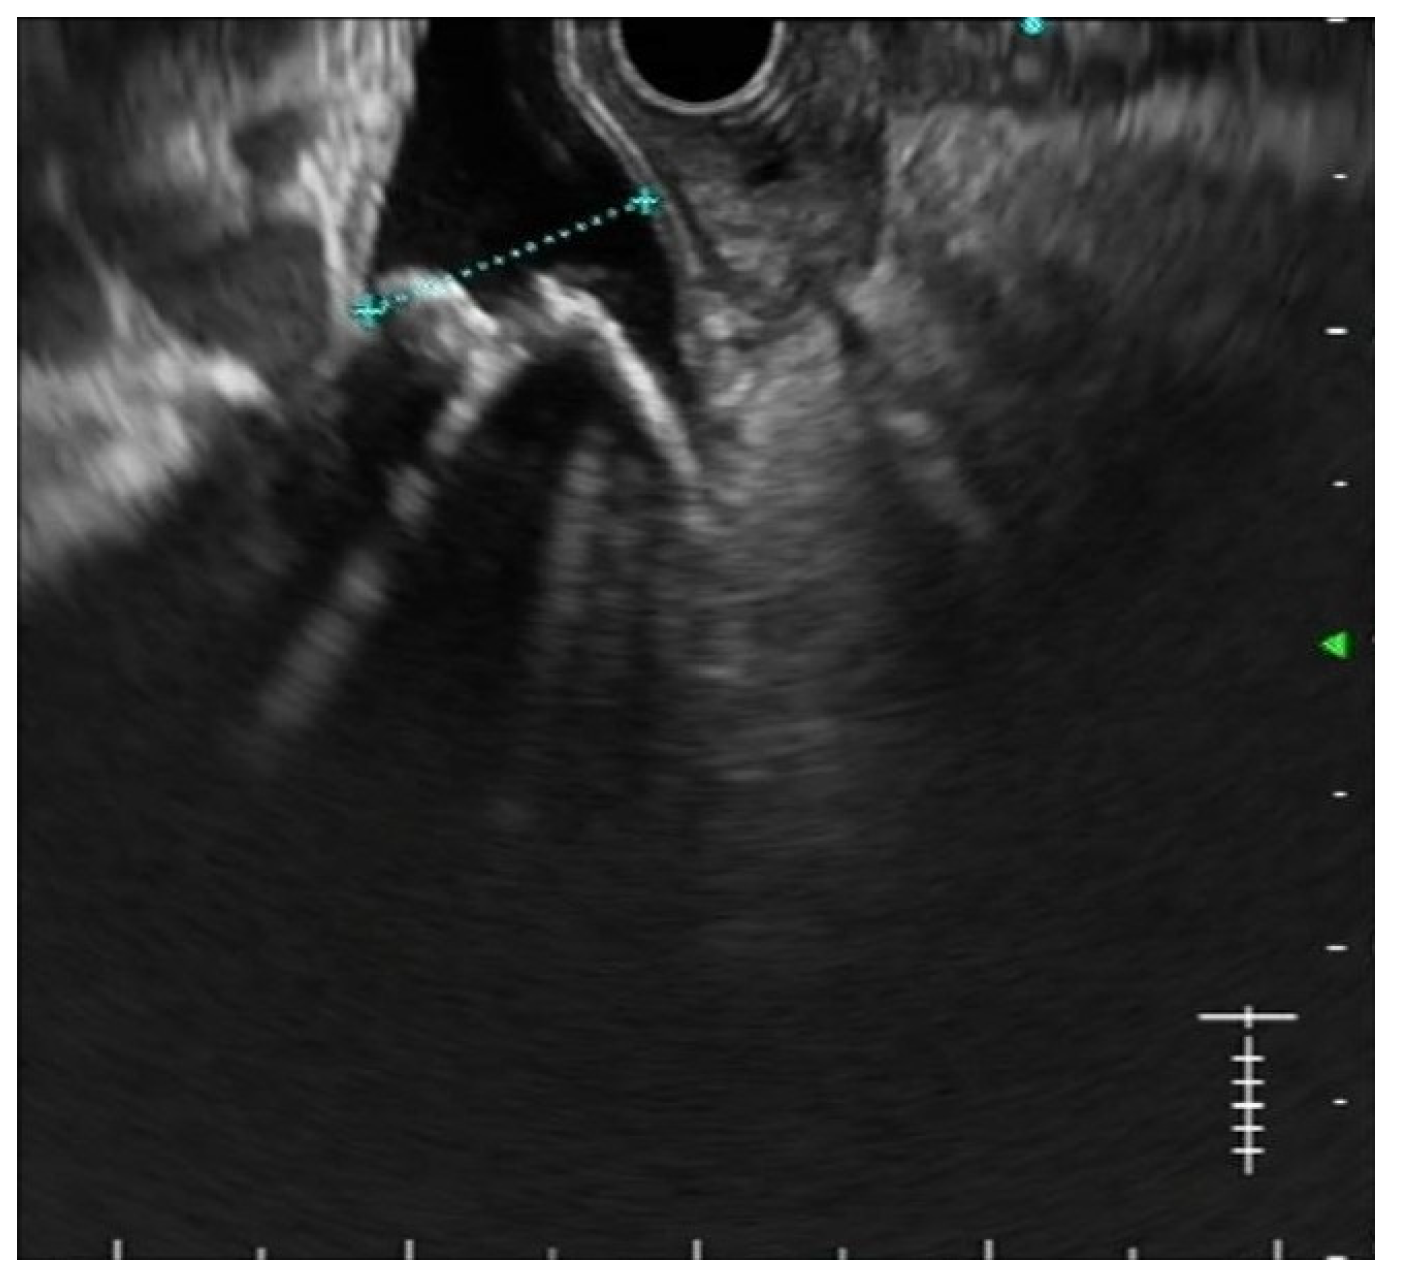

- Fusaroli, P.; Lisotti, A.; Syguda, A.; D’Ercole, M.C.; Maimone, A.; Fabbri, C.; Cennamo, V.; Cecinato, P.; Cariani, G.; Caletti, G.; et al. Reliability of endoscopic ultrasound in predicting the number and size of common bile duct stones before endoscopic retrograde cholangiopancreatography. Dig. Liver Dis. 2015, 48, 277–282. [Google Scholar] [CrossRef]